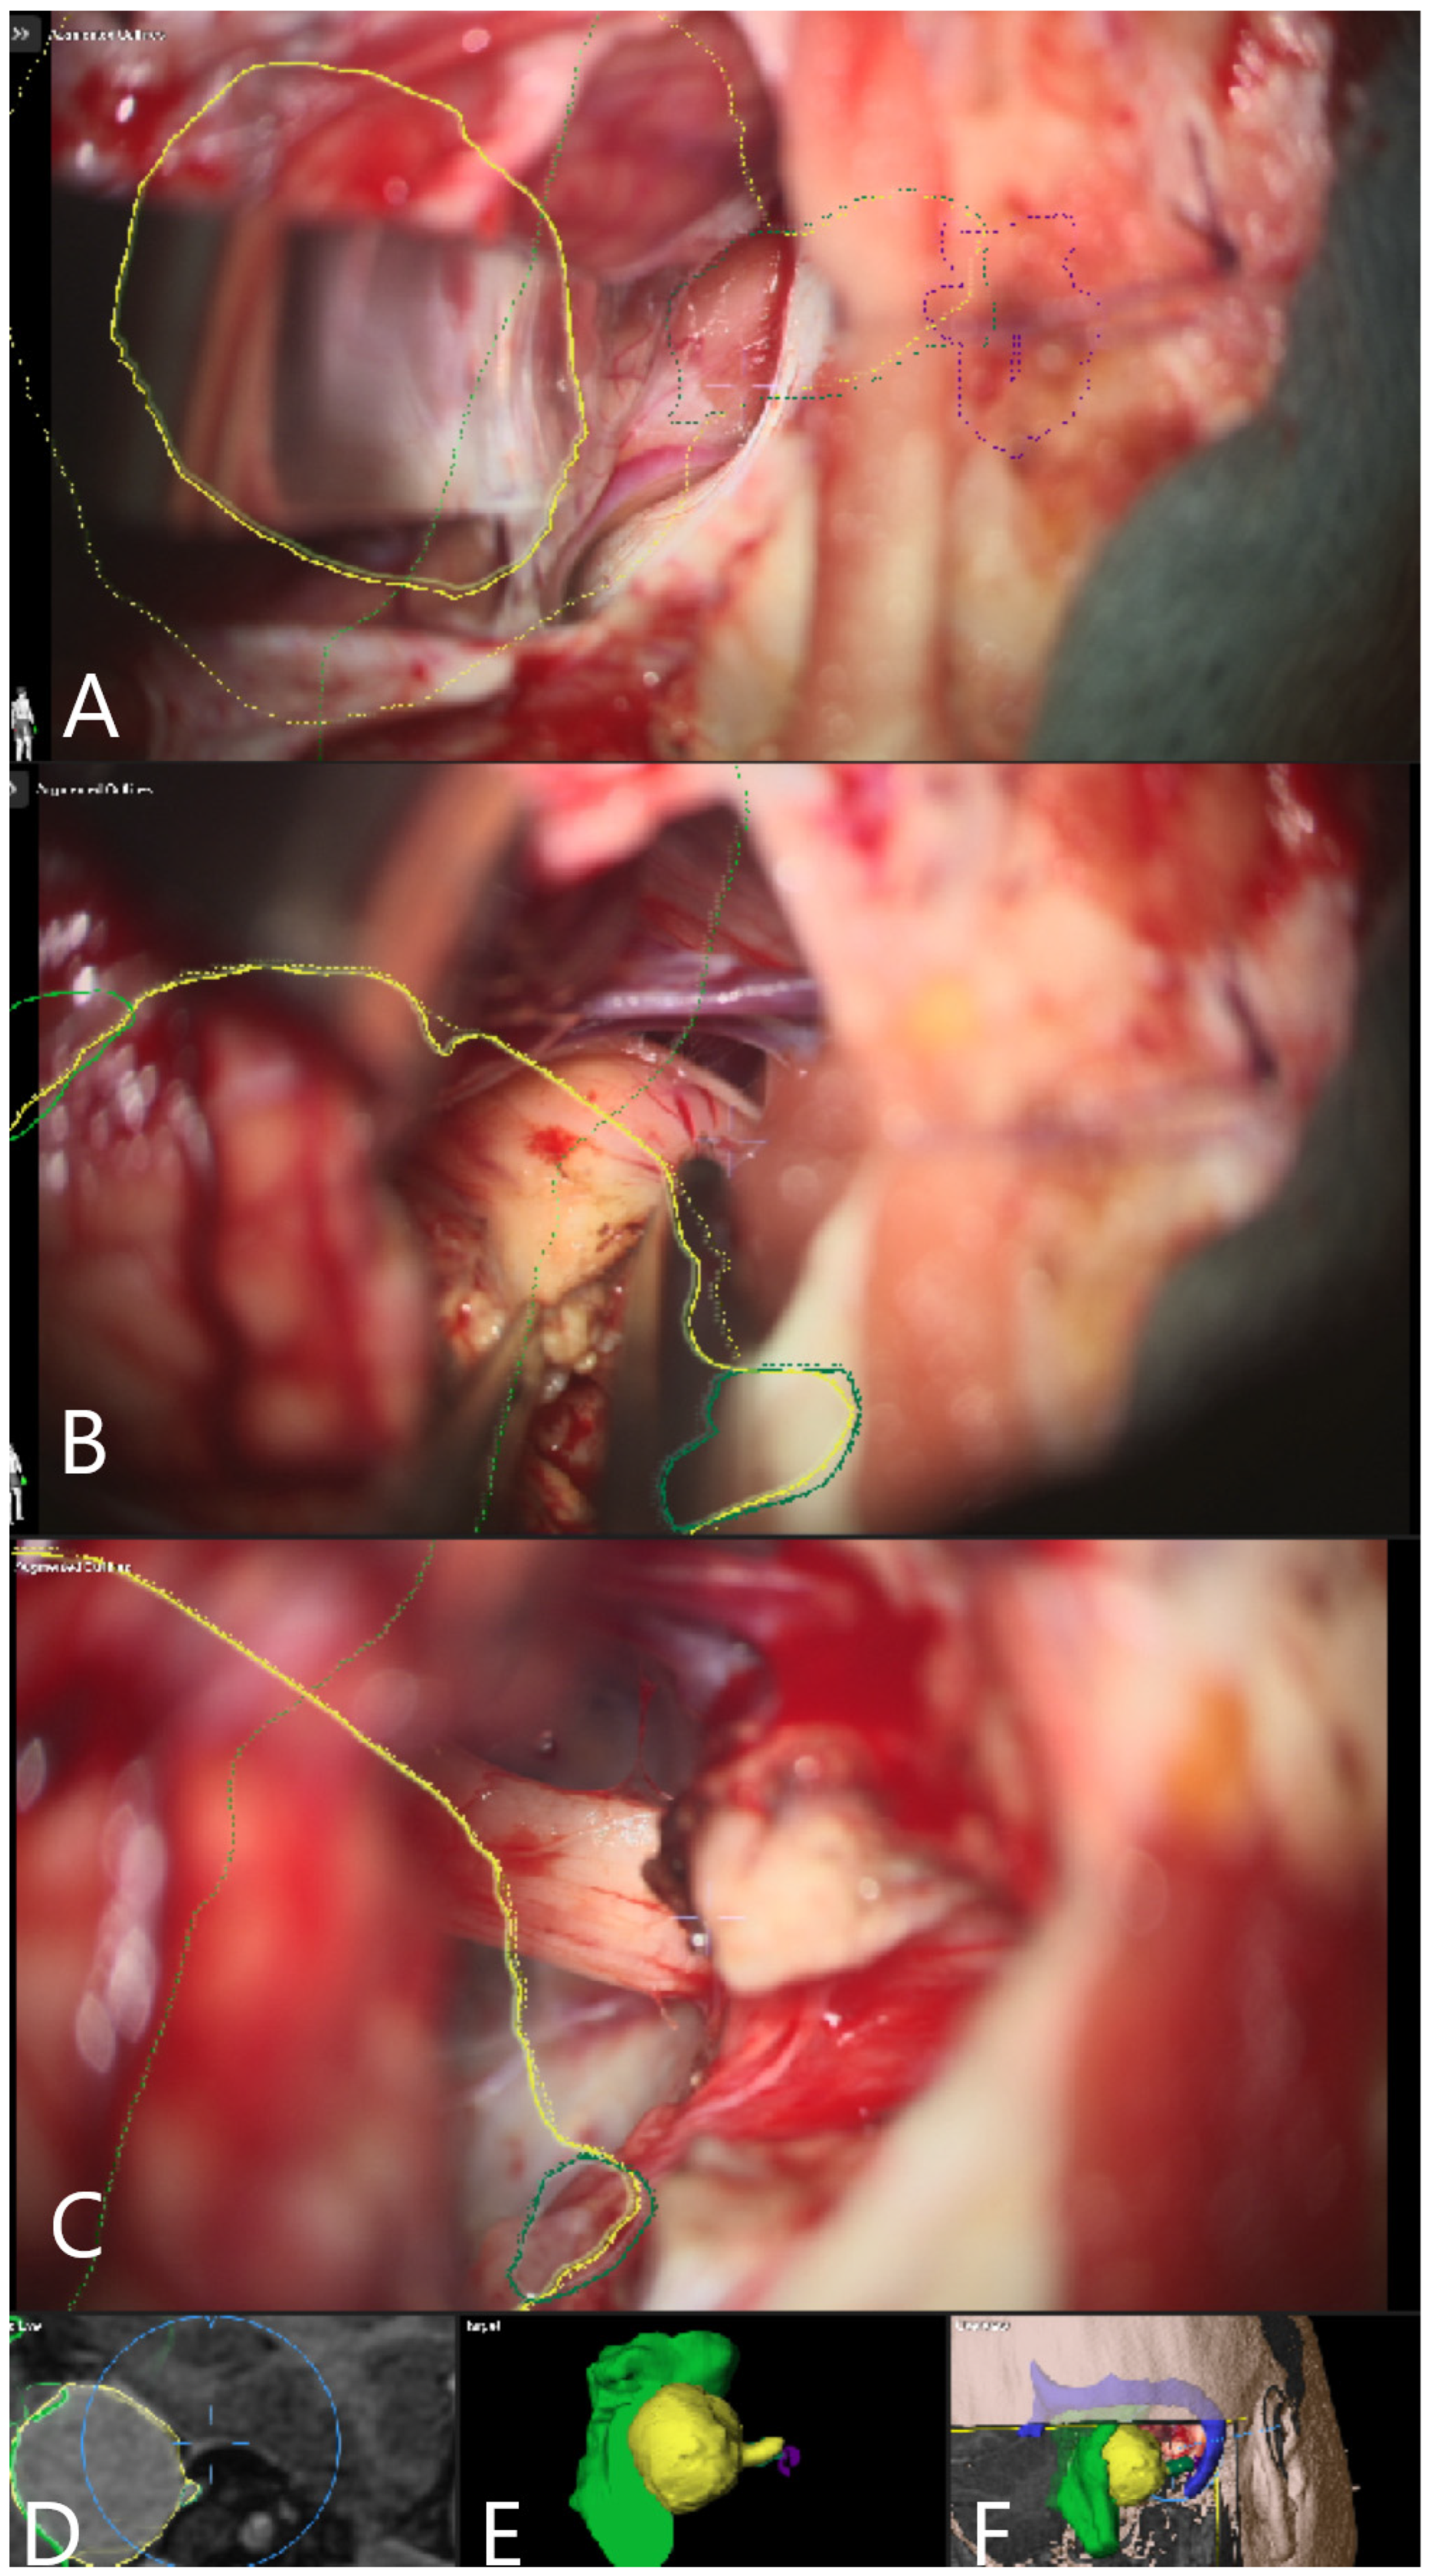

Illustrative Cases